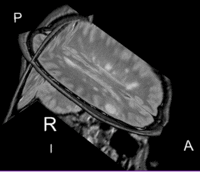

before registration: Orig. MRML Data tree after registration: Registered. MRML Data tree: exam 2 is within nested affine transforms

Lesion change visualization in 3DLesion change visualization in 3D